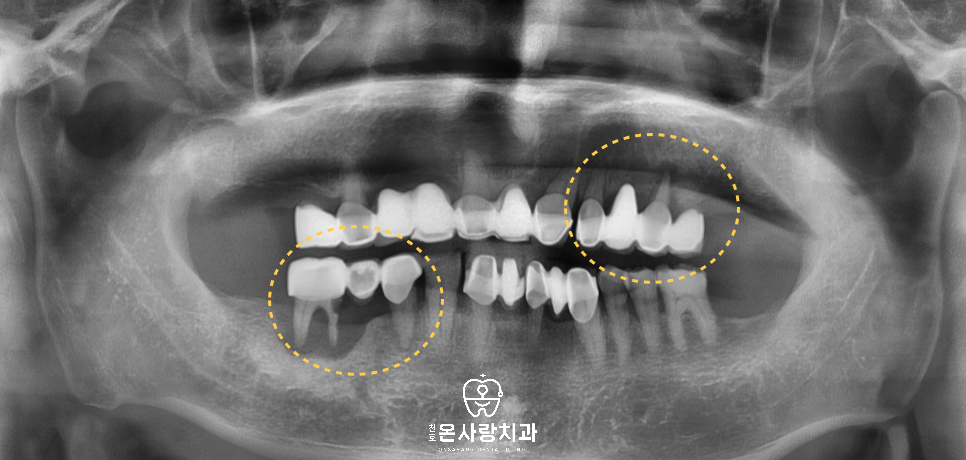

간단한 문진과 구강내

검진 후 올바른 상태를 파악하기 위해서

전체 파노라마 x-ray를 촬영하였습니다.

아래와 위에 걸쳐서 양쪽의

브릿지 하방에 위치한

잇몸뼈들이 치아 주변을

따라서 상당히 파괴되어

거의 남아있지 않은 것을

볼 수 있습니다.

브릿지의 뒷 부분에 위치한 치아들에서

치조골의 파괴가 뚜렷하게 관찰되었으나

앞니에 연결이 되어있는 상태이고,

전체적으로 신경치료가 되어있지 않아서

불편함이 심각한 상황이었습니다.